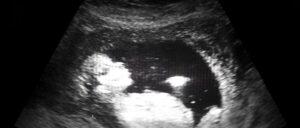

StatGen director Andrew Allen, Ph.D., professor of Biostatistics and Bioinformatics, collaborated with researchers at the Columbia University Vagelos College of Physicians and Surgeons to uncovered an array of new genes that cause stillbirth. This significantly increases the understanding of the condition’s genetic foundations. The findings suggest that genetic analysis could be used to counsel parents who have previously experienced stillbirth and to unlock new human biology. Their findings were published in The New England Journal of Medicine on August 12.